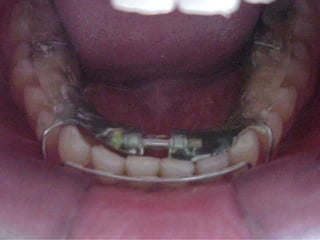

O documento apresenta registros odontológicos de um paciente ao longo de vários anos, incluindo panorâmicas iniciais e subsequentes, remodelações de arcadas dentárias superiores e inferiores ao longo de 7 meses, vedamentos labiais e registros de máxima intercuspidação e guias caninas nas datas listadas.